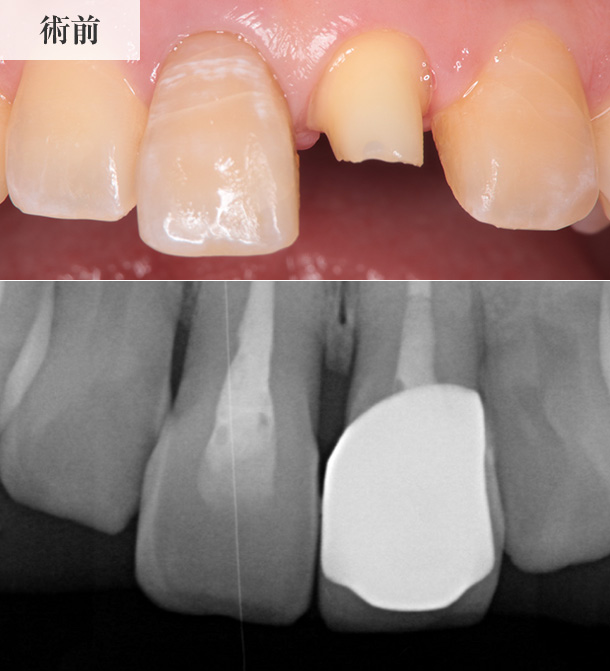

歯の神経が失われ、

人工物が充填されていた

前歯2本の歯髄再生治療を実施

※名古屋RD歯科クリニックでの症例

レントゲン画像

歯髄再生治療前の患歯のレントゲン画像です。

患歯である前歯2本には、歯の根(根管)の中に人工物が充填されているため、レントゲン画像では白く映し出されています。